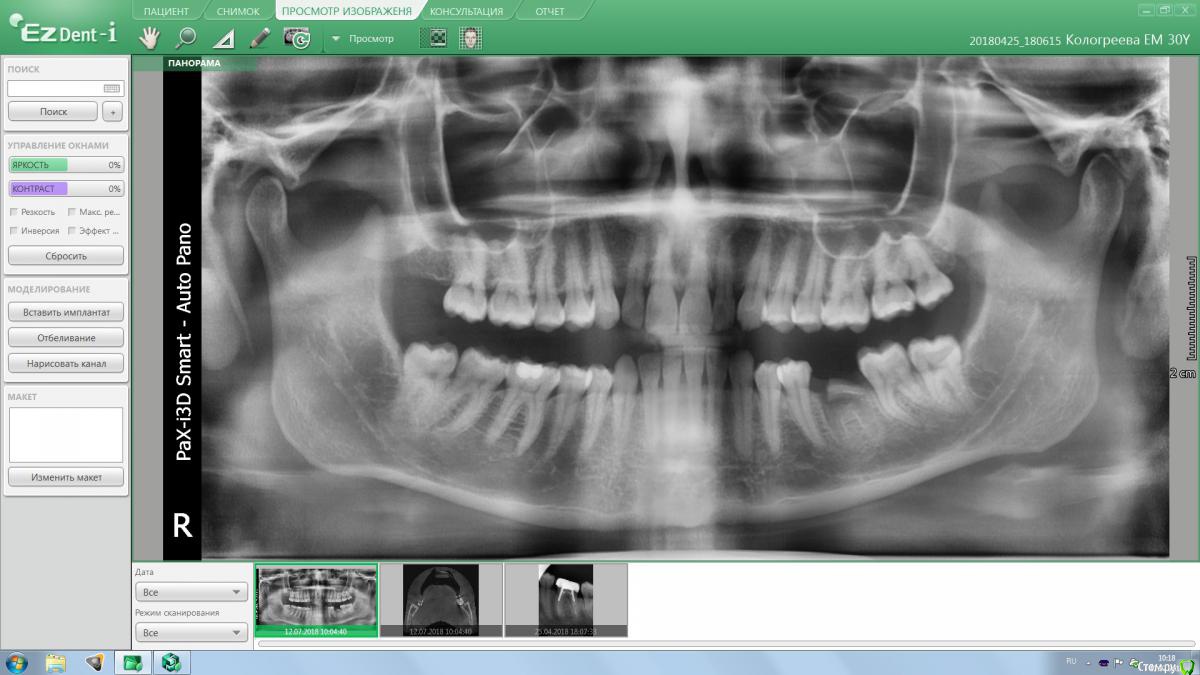

Astronaft Опубликовано 6 июля, 2018 Поделиться Опубликовано 6 июля, 2018 (изменено) Я пробовал один раз.Впечатления смешанные.1. просто в исполнении.2. Хорошо, быстро заживает. Есть ощущение что так можно проводить профилактику альвеолита.3 .Десны действительно достаточо.4. Кость - неоднозначно. Надо попробовать 2 рядом стоящих зуба "с шайбой" и "без".5. Шайба удаляется легко. Без анестетика, зондом поддел.6. Поверхность под шайбой - белая соед.тканная пленка. Рентген в день удаления -> фото через неделю -> фото через 2 месяца + КЛКТ ( срезы: перегородка и оба корня) http://miworks.weebly.com/uploads/1/6/8/7/16879370/x07221.jpg http://miworks.weebly.com/uploads/1/6/8/7/16879370/dscn6666_orig.jpg http://miworks.weebly.com/uploads/1/6/8/7/16879370/dscn6948_orig.jpg http://miworks.weebly.com/uploads/1/6/8/7/16879370/dscn6943_orig.jpg http://miworks.weebly.com/uploads/1/6/8/7/16879370/dscn6952_orig.jpg http://miworks.weebly.com/uploads/1/6/8/7/16879370/dscn6953.jpg http://miworks.weebly.com/uploads/1/6/8/7/16879370/dscn6954.jpg http://miworks.weebly.com/uploads/1/6/8/7/16879370/dscn6949_orig.jpg http://miworks.weebly.com/uploads/1/6/8/7/16879370/x07221-1.jpghttp://miworks.weebly.com/uploads/1/6/8/7/16879370/x07221-4.jpg http://miworks.weebly.com/uploads/1/6/8/7/16879370/x07221-2.jpghttp://miworks.weebly.com/uploads/1/6/8/7/16879370/x07221-3.jpg Изменено 6 июля, 2018 пользователем Astronaft 4 Ссылка на комментарий

annda Опубликовано 7 августа, 2018 Поделиться Опубликовано 7 августа, 2018 (изменено) Тоже попробовала.Застарелый перелом корня.Два свища на момент приема.Удаление всего,спилила на коронковом фрагменте до связки,канал закрыла IRMом,в дефект порошок Лилпласт на АPRF ,обратно фрагмент притопила,фиксация на ретейнер.Снимок через две недели.Теперь думаю,не длинноват ли фрагмент.Хотя,может и проекция снимка вводит в заблуждение.КТ срезы сняла с экрана,пардон за качество. Изменено 7 августа, 2018 пользователем annda 3 Ссылка на комментарий